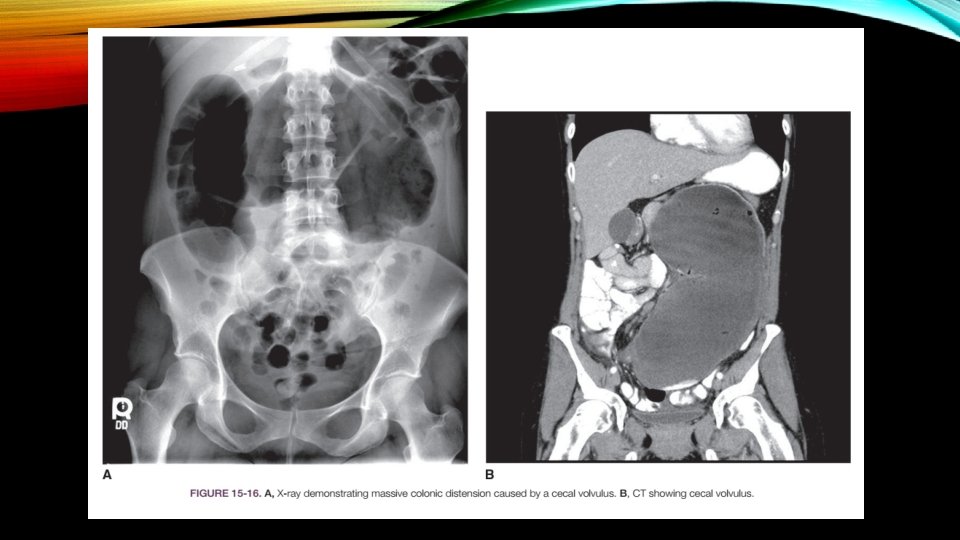

• Complete large bowel obstruction : ﺟﺮﺍﺣی ﻓﻮﺭی • Partial large bowel obstruction : ﻓﺮﺻﺖ ﺩﺍﺭیﻢ ﺗﺎ ﺑیﻤﺎﺭ پﺎیﺪﺍﺭ ﺷﻮﺩ ﻭ ﺑﺮﺭﺳی ﻫﺎی ﺑیﺸﺘﺮ ﺍﻧﺠﺎﻡ گیﺮﺩ Diagnosis : üPlain films of the abdomen : ﺳﺎﻧﺘی ﻣﺘﺮ ﺑﻮﺩ ﺟﺮﺍﺣی ﺑﺎیﺪ ﺻﻮﺭﺕ گیﺮﺩ 12 < ﺍگﺮ ﻗﻄﺮ ﺳکﻮﻡ ü Water-soluble contrast enema ü Colonoscopic examination plays a major role in Ogilvie’s syndrome (localized paralytic ileus of the colon without mechanical obstruction); otherwise, it is reserved for the occasional case of volvulus for decompression or those patients who may need colonic stent placement.

TREATMENT • IV fluids • NGT • Continuous observation until the diagnosis is established • Emergency laparotomy is undertaken for acute large bowel obstruction with cecal distension beyond 12 cm , severe tenderness , evidence of peritonitis, or generalized sepsis • Stent placement = large bowel obstruction due to cancer and without peritonitis

VOLVULUS OF THE LARGE INTESTINE • sigmoid (70%) • cecum (30%) • Volvulus accounts for 5% to 10% of cases of large bowel obstruction • second most common cause of complete colonic obstruction • Stretching and elongation of the sigmoid with age • patients who are confi ned to psychiatric institutions or nursing homes have an increased risk for this disease

DIAGNOSTIC STUDIES • Abdominal x-ray films (kidney bean appearance) • Watersoluble contrast enemas (funnel-like narrowing that often resembles a bird’s beak) • CT scan

TREATMENT • Sigmoidoscopy with rectal tube insertion • Strangulation or Perforation is suspected or if attempts to decompress the bowel are unsuccessful = Emergency operation • Cecal volvulus is always treated surgically, rarely with cecopexy (suturing the cecum to the parietal peritoneum) and most commonly with right hemicolectomy with ileotransverse colostomy